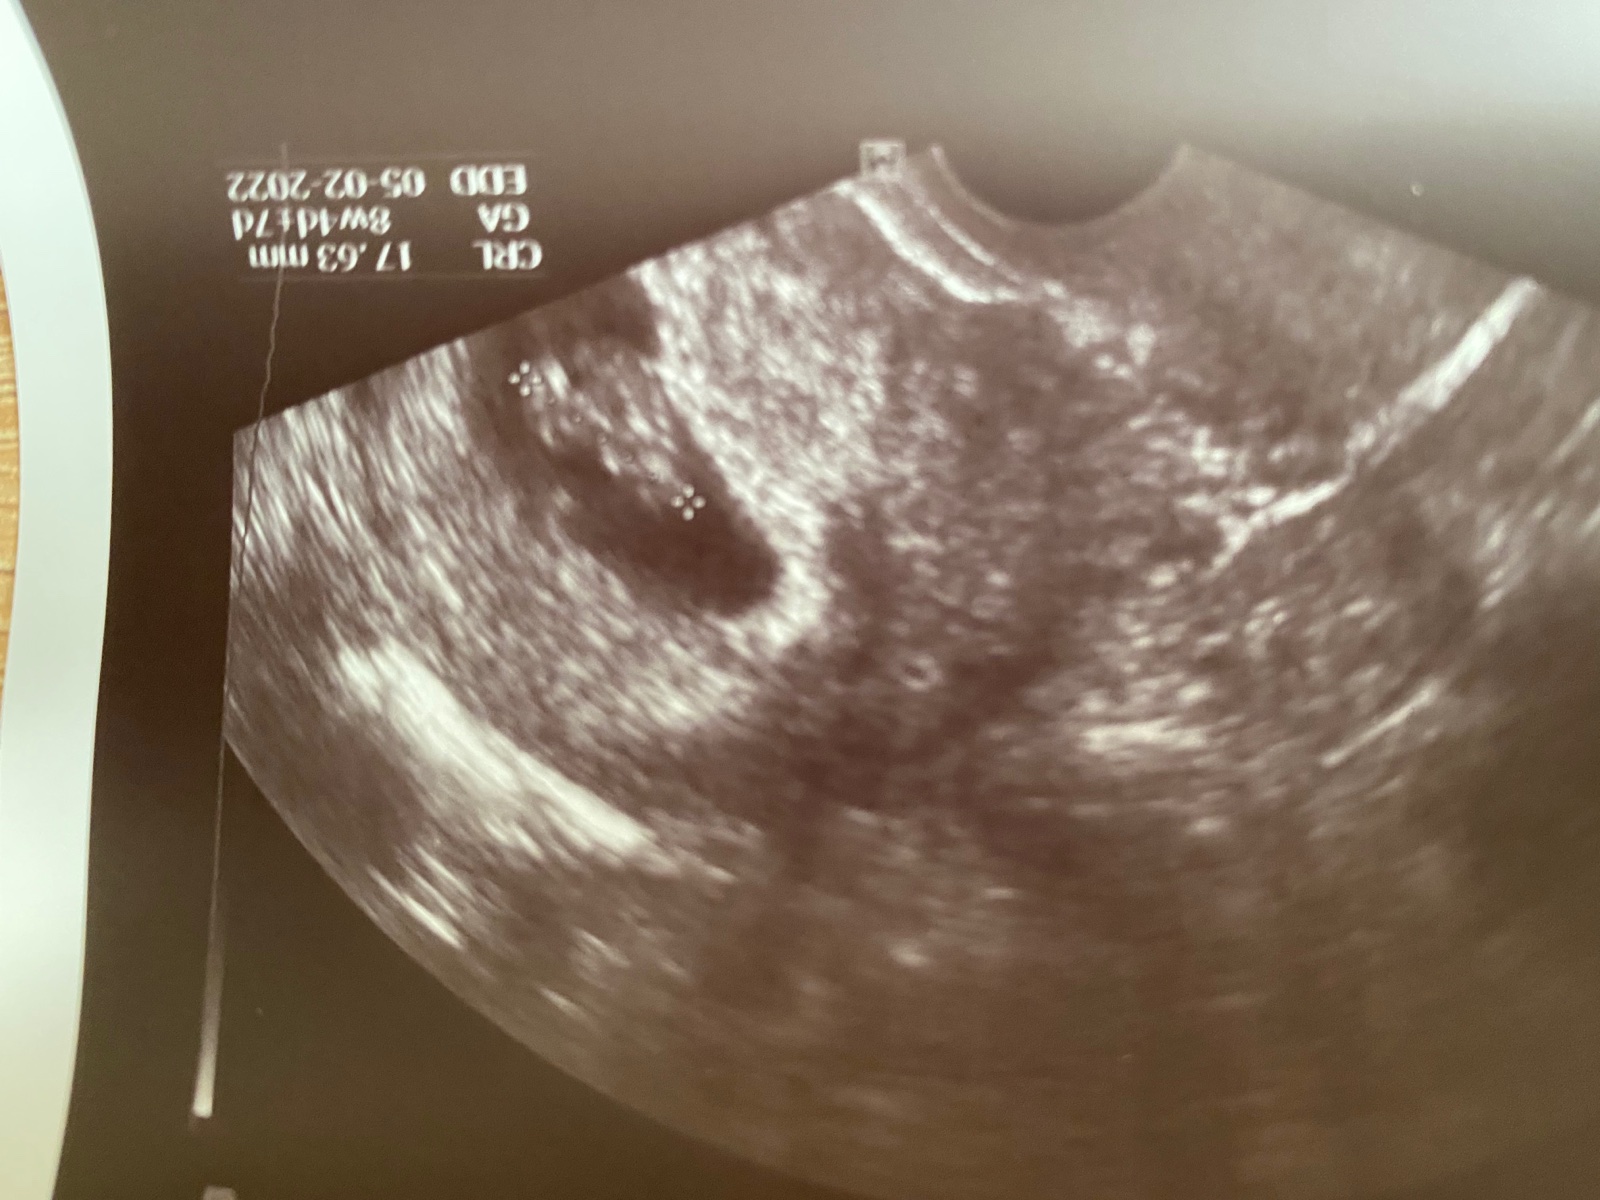

Ahoj vsechny co cekate 🙂.. rada se pridam k vam. Zitra jdu na muj 3ket a verim vic jak kdy jindy ze se nas mrazacek konecne uz zahnizdi jak ma a v dubnu bude s nama 😊